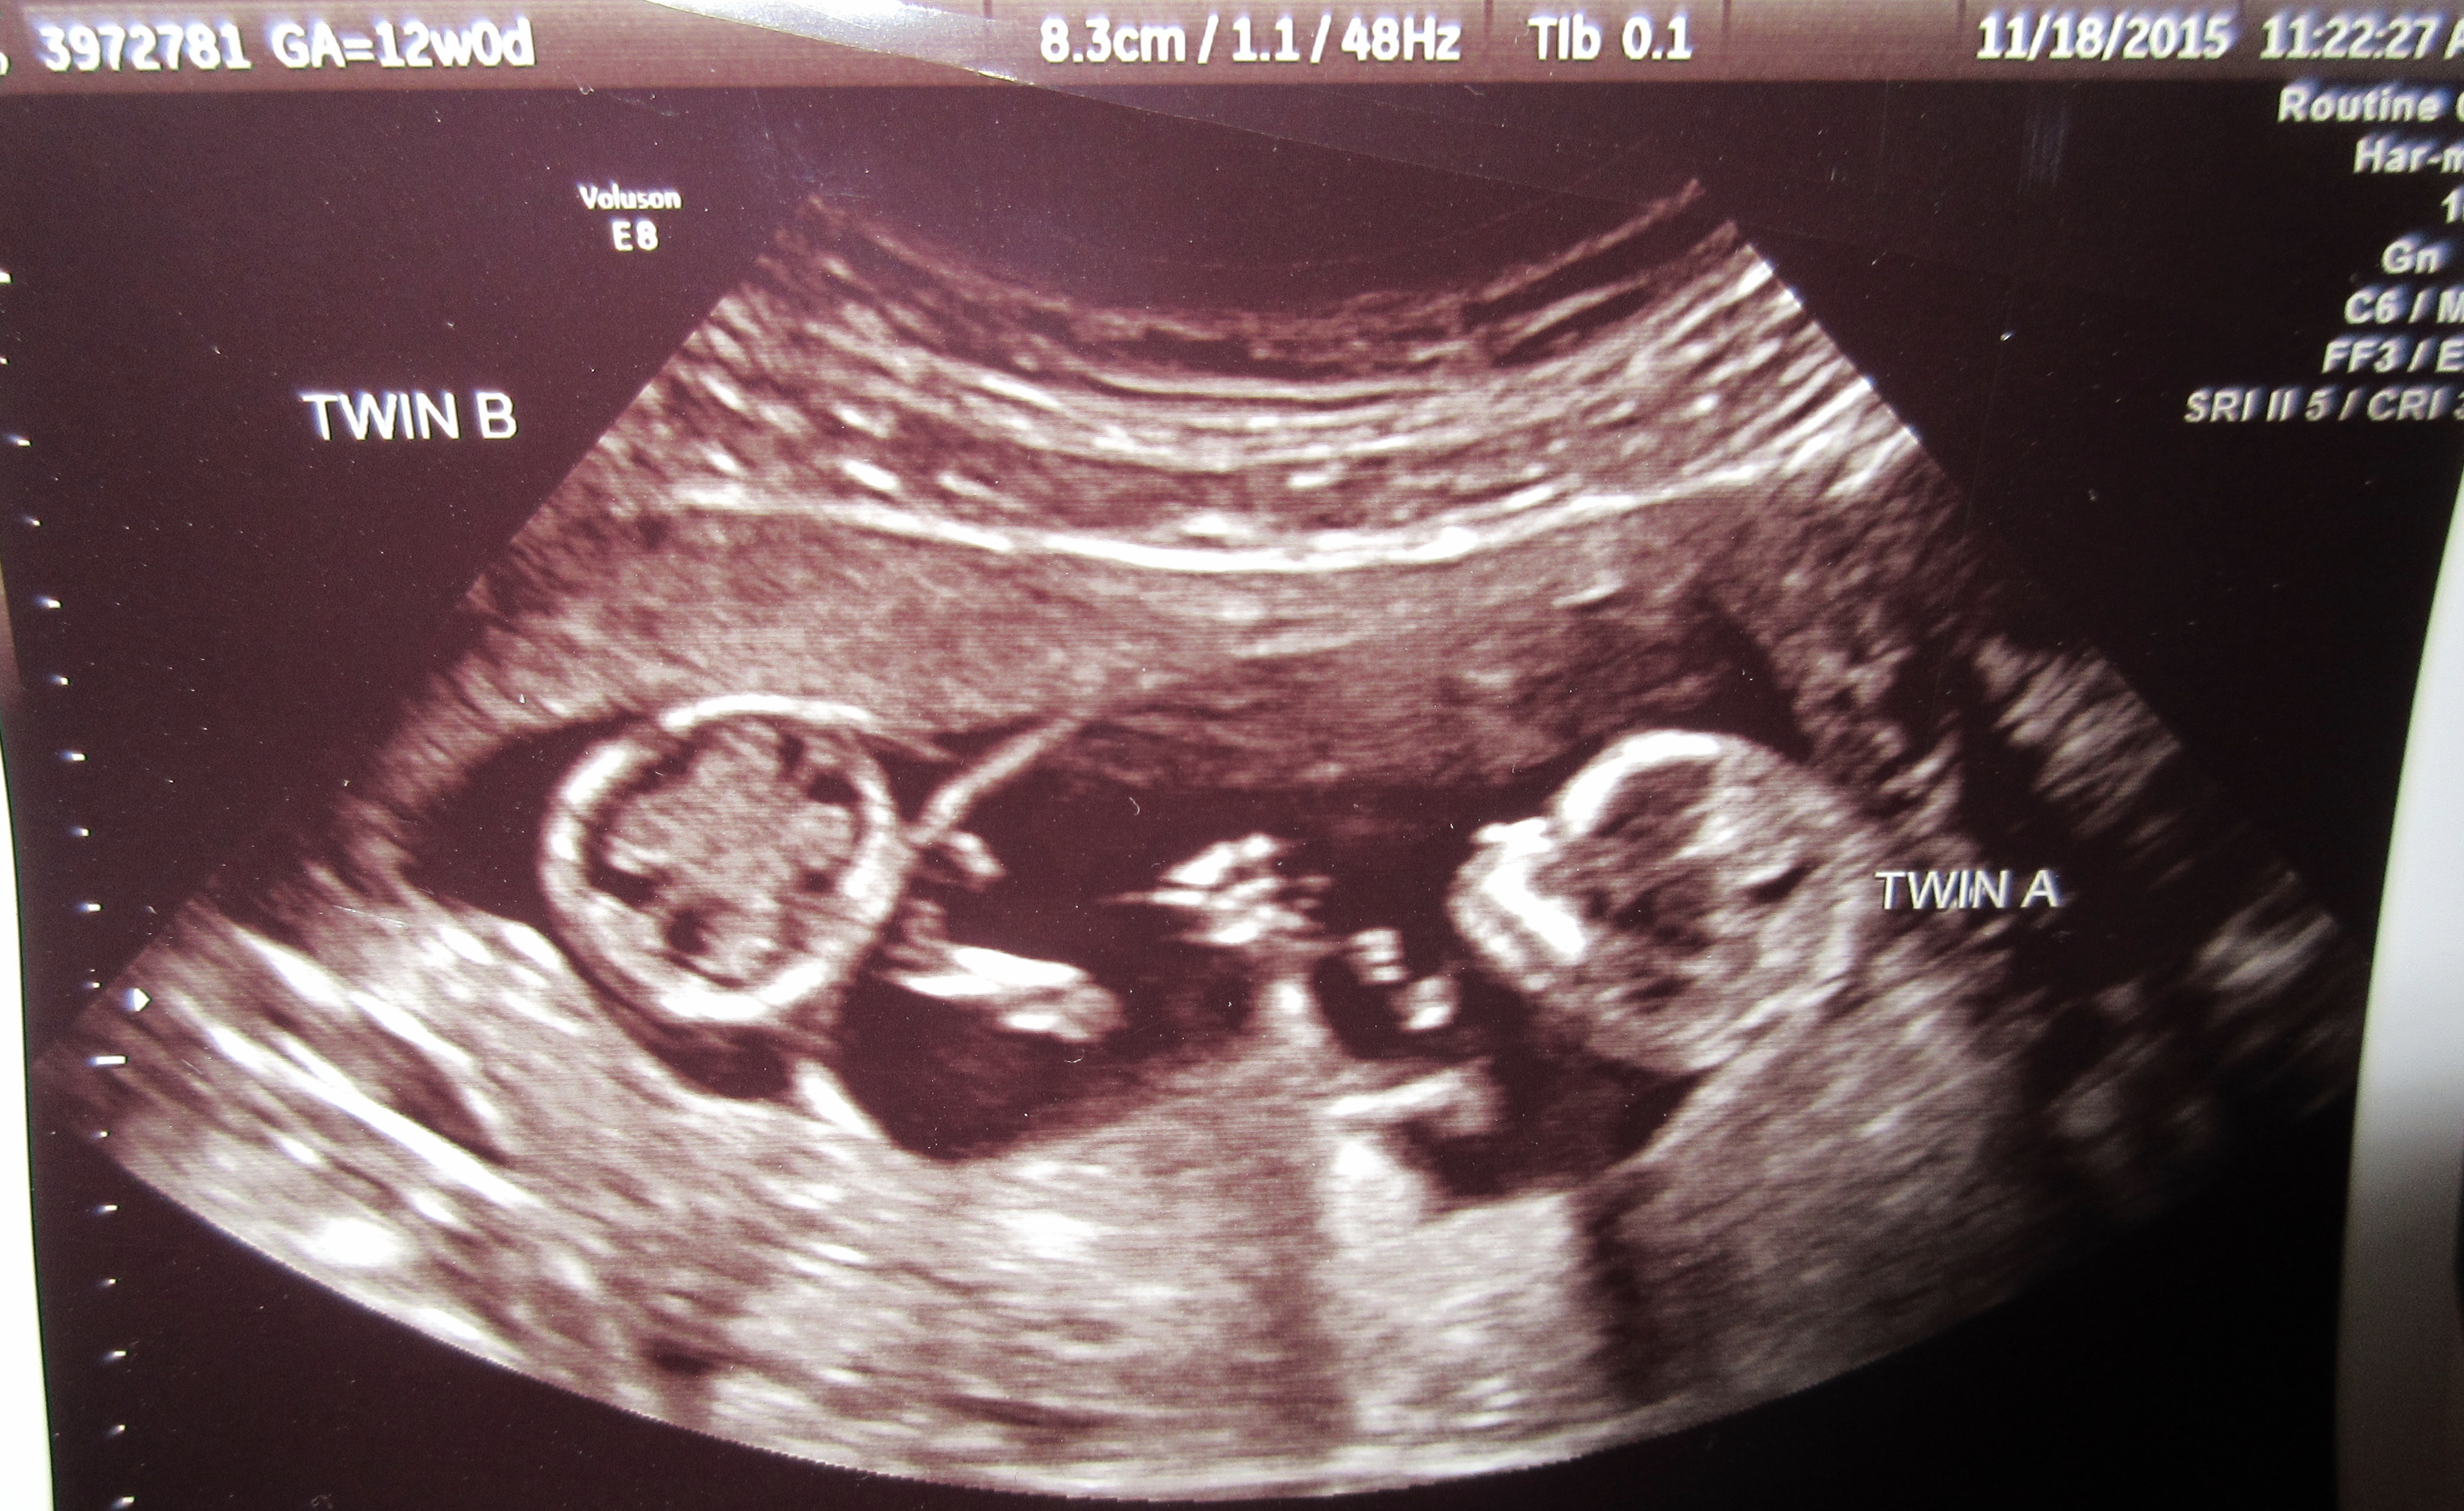

June 1st was my due date for a full term pregnancy, my csection was scheduled for May 18th (38 weeks), which I fully expected to make it too. But no way, my twins wanted to be born in April the day after my birthday. It was a non-eventful month, just lots of heartburn & odd sleep patterns, went to the dentist & tried to get my hospital pictures all set up. I woke up to pain & lots of liquid; my water had broke. I called my doctor at 7:00am expecting to be able to stay home (naive FTM), but I was told to go to the hospital.

Upon checking in I saw my doctor & tried to negotiate a vaginal birth but he wouldn’t do it. Twin A was transverse breech, therefore there was no way he would deliver any way but csection. During prep I was given an antacid to help with heartburn, but I had a premonition this was not going to go well. As I laid down to begin the procedure I started to feel nauseous all over AGAIN. I held myself together long enough to get the babies out, then the true adventure began.

Twin A was born at 10:58am & Twin B 10:59am. Both were screaming & healthy. It was the most amazing moment of my life to see this pregnancy come to an end, resulting in my beautiful little boy & girl.